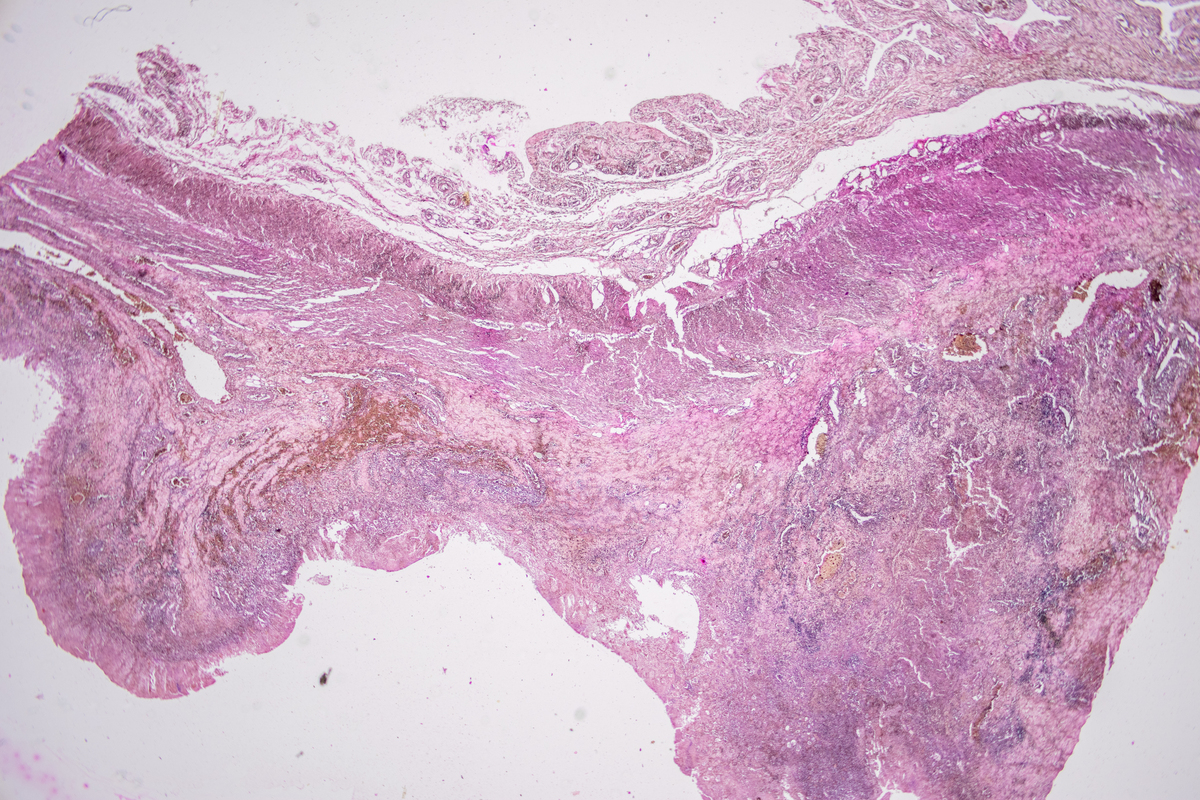

子宫肌瘤特殊类型:富细胞性、静脉内平滑肌瘤、播散性腹膜平滑肌瘤

子宫肌瘤的特殊类型包括:

• '富细胞性'

• '静脉内平滑肌瘤'

• '播散性腹膜平滑肌瘤'